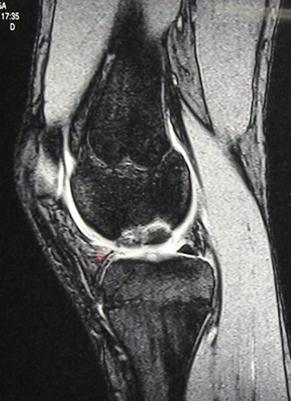

Le bilan d'imagerie (radiographies, IRM , arthroscanner ou arthroIRM) permet de préciser l'étendue

de la lésion, l'état de la surface cartilagineuse, la vitalité du fragment et le potentiel de croissance résiduelle (Figure 1). La classification de Bédouelle en 4 stades permet les choix thérapeutiques (Figure 2).

Figure 1 : Radiographies (à gauche) et IRM (à droite) d'une ostéochondrite du condyle interne chez un garçon de 14 ans